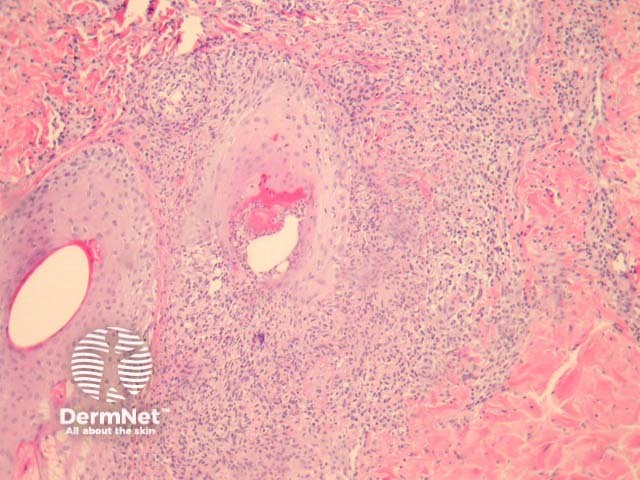

The follicles are often plugged but there is minimal other epidermal change. There is a suppurative folliculitis, primarily involving the infundibular portions of the hair follicle (figures 1, 2, 3 show the same process at progressively higher magnification). PAS stain reveals numerous oval yeast-like organisms within the follicle and often in the surrounding dermis (figure 1, inset). The yeasts have been compared to a “clown with clown nose” as there is often small budding of the yeast-like forms (figure 1, arrow). The surrounding dermis shows a reactive inflammatory reaction which may be exuberant if there is follicular rupture.

Figure 2